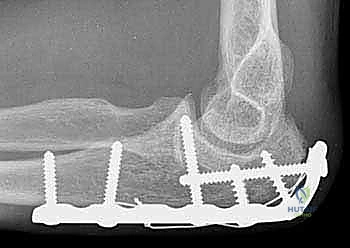

TECH FIG 3 • A. A lateral radiograph illustrates a comminuted olecranon fracture with a small proximal olecranon fragment. B. An oblique view shows the fragmentation. C. A 3.5-mm limited-contact dynamic compression plate and screws contoured to wrap around the dorsal surface of the olecranon is used for fixation. (continued)

"Now, let's select our plate. A 3.5-mm limited-contact dynamic compression plate (LC-DCP) or a precontoured olecranon plate is typically used. We need to contour the plate to wrap intimately around the proximal aspect of the olecranon. This anatomical contouring is vital for stable fixation."

• Proximal Fixation: "A straight plate will only allow for two or three screws in the metaphyseal bone proximal to the fracture. By bending the plate around the proximal aspect of the olecranon, we gain additional screw purchase in the proximal fragment. The most proximal screws can be quite long, crossing the fracture line into the distal fragment, achieving bicortical purchase. In some cases, these screws can be directed to engage the anterior ulnar cortex, providing excellent purchase."

• Distal Fixation: "Distally, we'll secure the plate to the ulnar diaphysis. Ensure at least 3-4 bicortical screws are placed distal to the fracture for adequate working length and stability."